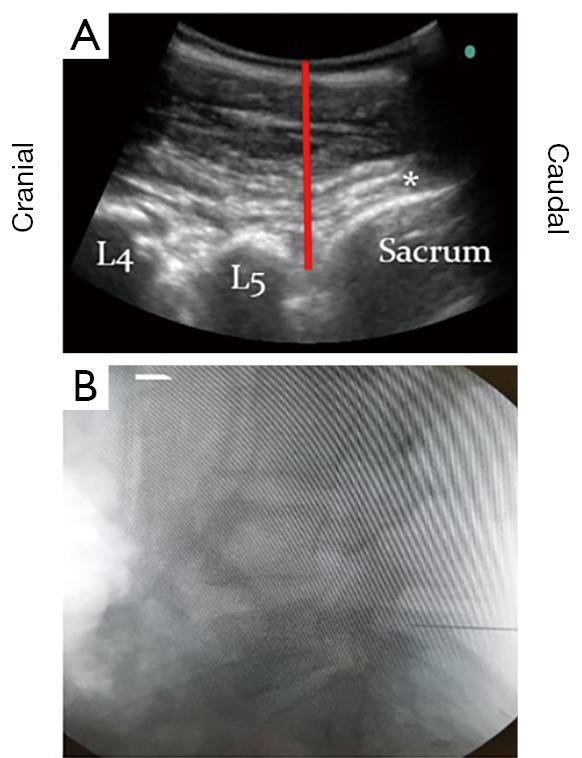

Lumbar spinal surgery relies on palpation of anatomical landmarks and X-ray imaging confirmation to identify the correct spinal level, therefore exposing patients and staff to radiation, and increasing intraoperative time and cost. Ultrasound (US) assistance is being used to visualise spinal anatomy by many specialities, such as neurology and anaesthetics, and can be used intraoperatively in selected spinal surgery cases. However, its potential use to check spinal levels prior to surgery remains understudied. This prospective, pilot study screened all patients requiring a primary elective or emergency lumbar discectomy, under the supervision of a single consultant neurosurgeon, over an 8-month period at a single neurosurgical unit. US assistance was used to identify and mark the proposed spinal level prior to skin incision. The resemblance of the parasagittal lumbar US images to the back of the dinosaur Stegosaurus aided users in identifying the relevant anatomical structures necessary to mark the desired spinal level, (e.g., lumbar laminae, intervertebral spaces, sacrum). This inspired our description of the US images of the lumbar spine as 'The Stegosaurus Appearance'. The spinal level marked by US was then confirmed in the standard fashion using intraoperative X-ray imaging. In 100% of cases (12/12), the desired spinal level was correctly identified using US, confirmed by the subsequent intraoperative X-ray images. US assistance appears to be a safe, quick, and accurate tool for identifying the correct lumbar spinal level prior to skin incision, and could therefore represent a useful adjunct to supplement level checking in lumbar spinal surgery.

腰椎手术依靠触诊解剖标志并通过X射线成像确认来确定正确的脊柱节段,因此会使患者和工作人员暴露于辐射之下,同时增加手术时间和成本。超声(US)辅助正被许多专业领域用于可视化脊柱解剖结构,如神经科和麻醉科,并且可在某些脊柱手术病例中用于术中。然而,其在手术前检查脊柱节段的潜在用途仍未得到充分研究。这项前瞻性试点研究在一个神经外科单元对所有需要进行初次择期或急诊腰椎间盘切除术的患者进行了筛查,为期8个月,由一位神经外科顾问医生监督。在皮肤切口前,使用超声辅助来识别并标记拟手术的脊柱节段。腰椎矢状旁超声图像与剑龙背部的相似性帮助使用者识别标记所需脊柱节段所需的相关解剖结构(例如,腰椎椎板、椎间隙、骶骨)。这激发了我们将腰椎超声图像描述为“剑龙外观”。然后使用术中X射线成像以标准方式确认超声标记的脊柱节段。在100%的病例(12/12)中,使用超声正确识别了所需的脊柱节段,并得到了随后术中X射线图像的证实。超声辅助似乎是一种在皮肤切口前识别正确腰椎脊柱节段的安全、快速且准确的工具,因此可能是腰椎脊柱手术中补充节段检查的有用辅助手段。